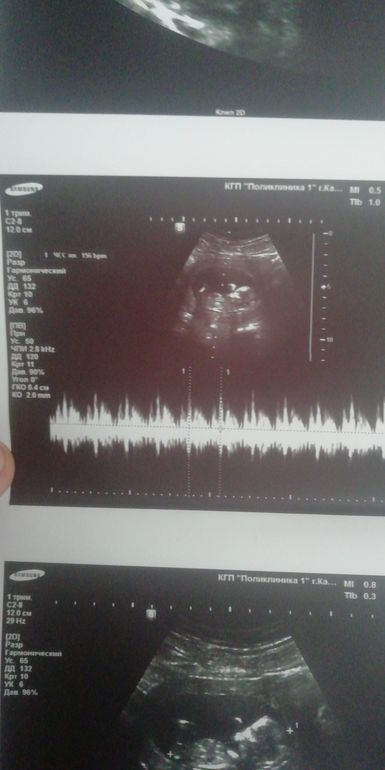

Узи 12 н4 дня, погадайте кто будет))

Прошли скрининговое узи, все хорошо) совпадает срокам чс 156, погадайте кто будет))